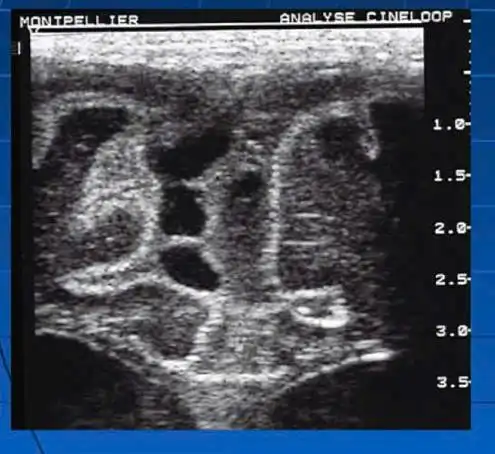

Một số hình ảnh tổn thương não phát hiện qua siêu âm thóp